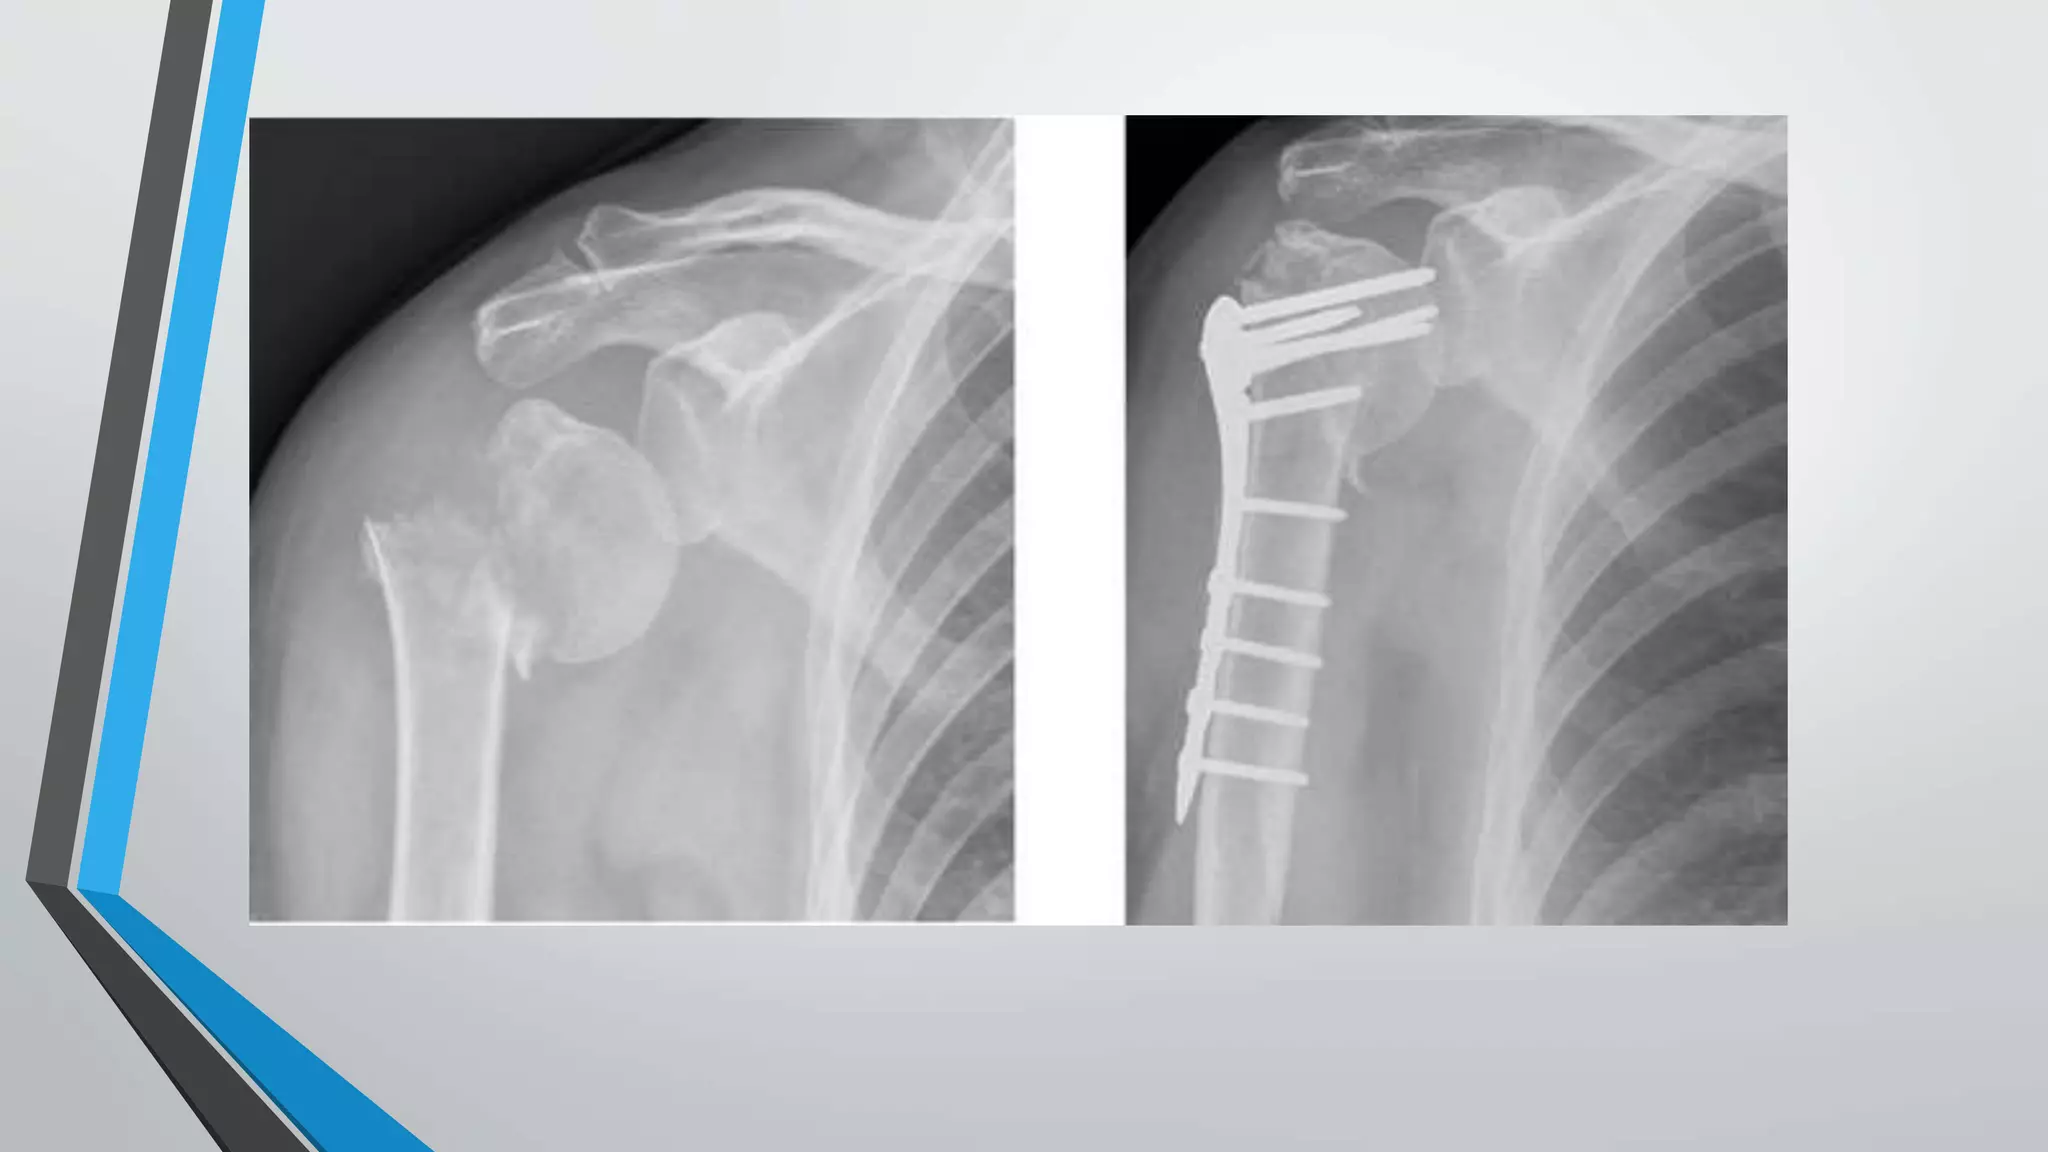

Fixation using proximal humerus locking

plate[PHILOS PLATING]

• The inability of conventional plates and screws to resist varus deforming forces in the

proximal humerus,particularly if the bone is osteoporotic ,has led to locking plate fixation

being used for these fractures

• Several clinical studies have shown high rates of healing and excellent functional

recovery with proximal humerus locking plates.

• Plate designs vary in terms of the number of proximal screws and their arrangement ,as

well as the ability to place screws at different angles with regard to the plate

• A plate is selected to allow at least three screws to be placed into the distal shaft

segment .the plate position is also selected to avoid subacromial impingement and to

allow two screws to be placed into inferomedial aspect of the humeral head

• A minimum of five or six screws are routinrly placed into the proximal segment .screw

placement should be performed by drilling through the near cortex only,this avoids

perforation of the articular surface.

• Once the plate and the screws have been placed transtendinous sutures are tied onto

the plate to provide additional fixation